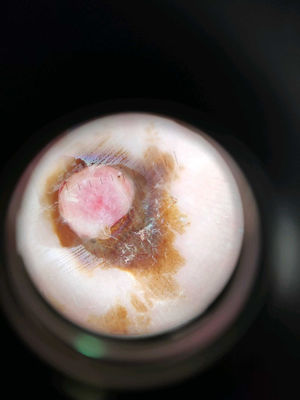

A la exploración se apreciaba una pápula rosada sobre una mácula pigmentada en la palma izquierda (fig. 1). Con la dermatoscopia se observaba una lesión rosada central sobre una mancha pigmentada que ocupa los dermatoglifos (fig. 2).

Se reinterrogó a la paciente sobre la lesión, refiriendo que debido al sangrado precisó acudir a urgencias hospitalarias donde coagularon la lesión con nitrato de plata.

Ante esta exploración y anamnesis, con sospecha de hemangioma capilar lobular con pigmento exógeno perilesional, se realizó un afeitado de la lesión y posterior electrocoagulación. El diagnóstico anatomopatológico confirmó que se trataba de un hemangioma capilar lobular. No se apreció recidiva tras 2 años del procedimiento.

Durante un sangrado agudo de la lesión, se pueden utilizar diferentes herramientas para coagularla y parar el sangrado. Entre estas herramientas se encuentra el nitrato de plata, el cual provoca una pigmentación exógena debido al depósito de partículas de plata en el estrato córneo de la epidermis. Esta pigmentación da lugar a unas máculas marrón-grisáceas que pueden simular lesiones melanocíticas, principalmente un melanoma4. Por ello, es necesaria una buena anamnesis para poder hacer un correcto diagnóstico diferencial y evitar diagnósticos incorrectos, así como procedimientos invasivos innecesarios.